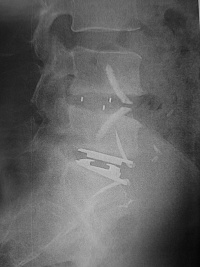

Prothese de profil

Exemple de Prothèse discale :

prothèse L5-S1 vue de profil